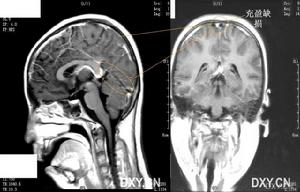

小兒病毒性腦炎--影像1.嗜睡